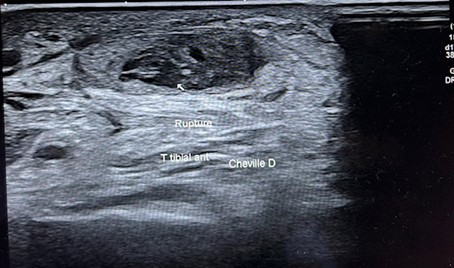

Rupture du tendon du muscle tibial antérieur droit : épaississement du tendon , moignon rétracté (cheville droite)

Vacuité de la gaine : rupture du tendon avec moignon ascensionné et non visible en coupe distale du tendon